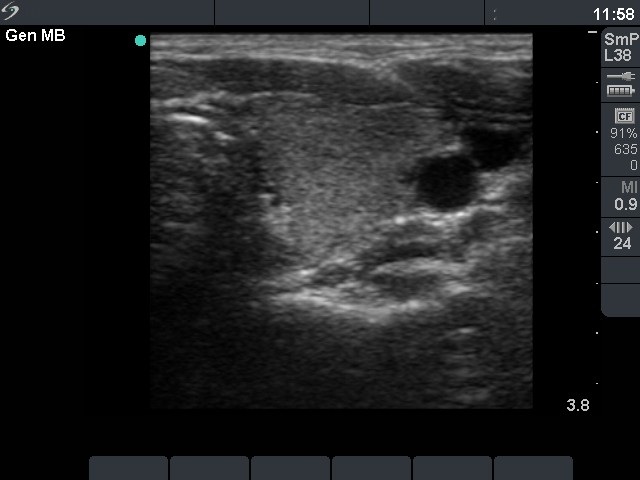

Follow-up investigation 18 months after first visit (ultrasonographic picture 4)

Patient on daily 5 mg methimazole therapy in euthyroid state

Left lobe, transverse scan. There are minimally-moderately hypoechogenic areas in the otherwise echonormal background.